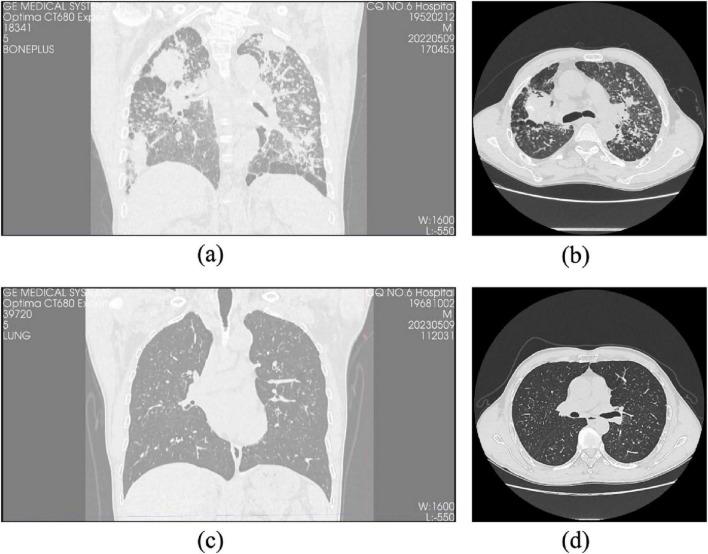

This study aims to develop a machine learning (ML) model that integrates computed tomography (CT) radiomics with clinical features to predict the progression of pulmonary interstitial fibrosis in patients with coalworker pneumoconiosis (CWP).

Clinical and imaging data from 297 patients diagnosed with CWP at The First Affiliated Hospital of Chongqing Medical and Pharmaceutical College between December 2021 and December 2023 were analyzed. Of these patients, 170 developed pulmonary interstitial fibrosis over a 3-year follow-up and were classified as the progression group, while 127 patients showed stable conditions and were classified as the stable group. The patients were divided into a training cohort ( = 207) and a test cohort ( = 90). Radiomic features were extracted from CT images of lung fibrosis lesions in the training cohort. These features were reduced in dimensionality to construct morphological biomarkers. ML methods were then used to develop three models: a clinical model, a radiomics model, and a multimodal joint model. The performance of these models was evaluated in the test cohort using receiver operating characteristic (ROC) curves and decision curve analysis (DCA).

In the training cohort, the area under the curve (AUC) for the clinical, radiomics, and joint models were 0.835, 0.879, and 0.945, respectively. In the test cohort, the AUC values for these models were 0.732, 0.750, and 0.845, respectively. The joint model demonstrated the highest predictive performance and clinical benefit in both the training and test cohorts.

The multimodal model, combining CT radiomics and clinical features, offers an effective and accurate tool for predicting the progression of pulmonary fibrosis in CWP.